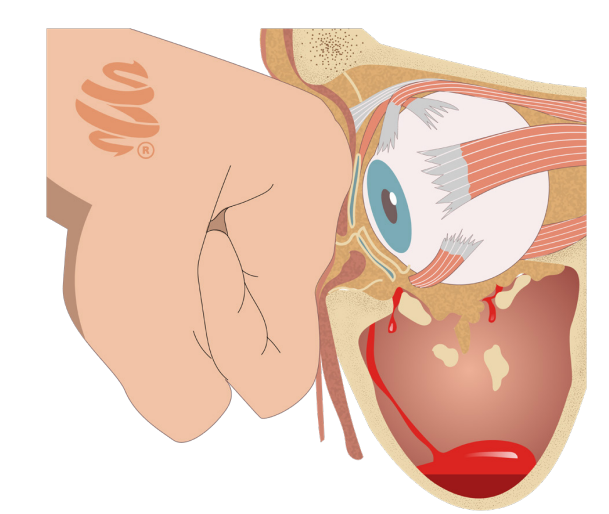

- Hematoma retrobulbar: Acúmulo de sangue atrás do globo ocular que pode levar à perda de visão definitiva.

- Encarceramento do músculo reto inferior: Comum em fraturas do assoalho da órbita, causa diplopia e pode induzir o reflexo óculo-cardíaco (bradicardia, náuseas).

- Fratura Orbital: A órbita é composta por 7 ossos, sendo as paredes medial e inferior as mais frágeis. A fratura do tipo “Blow-Out” ocorre por um aumento súbito da pressão intraorbital, que leva à fratura dessas paredes frágeis e herniação do conteúdo orbitário para os seios maxilar e etmoidal. Os sinais clássicos incluem diplopia, enoftalmia (afundamento do globo ocular) e restrição da motilidade ocular, especialmente na elevação do olhar, devido ao encarceramento do músculo reto inferior.